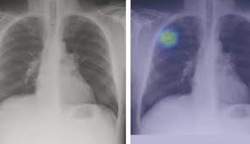

هم اکنون مقدار بالای آلاینده های منتشره از منابع ثابت (صنایع، کوره های آجر پزی و ...) و خودروها در استان علاوه بر آثار بسیار مضری که برای محیط زیست دارد، بشدت سلامتی مردمان این دیار را با خطر رو به رو ساخته است به طوری که عامل اصلی مرگ و میر بیماران قلبی و عروقی، تنفسی و سرطان ها در استان، آلودگی هواست .

فوق تخصص بیماری‌های خون و سرطان در یزد می گوید: گفت: استان یزد در ۱۰ سرطان شایع کشور، رتبه‌های اول تا سوم را دارد که ناشی از عوامل محیطی و ژنتیکی است.

وی اظهار داشت: عدم وجود فضای کافی ورزشی و کمبود فعالیت ورزشی به صورت عمومی، میزان بالای سرانه مصرف گوشت قرمز، استفاده زیاد از فست فودها، و غذاهای ناسالم و آلودگی هوای ناشی از صنعت و ترافیک هم از دلایل دیگر بالا بودن ابتلای به سرطان در این استان است.